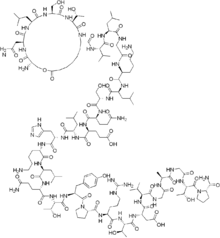

| Formula | C148H244N42O47 |

| Molar mass | 3363.827 g·mol−1 |